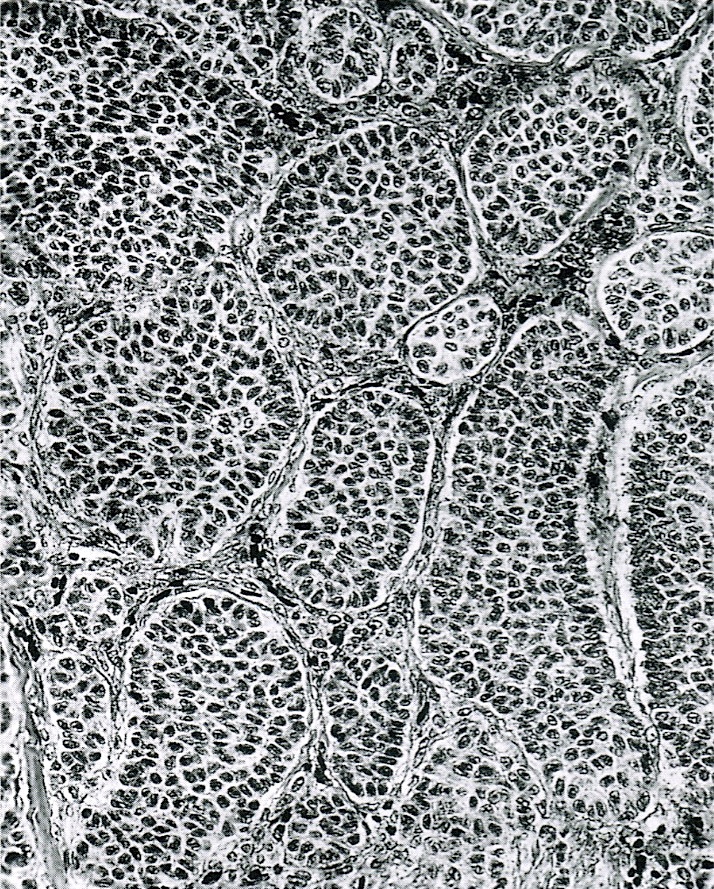

- Small, bland, cuboidal to polygonal cells with scant cytoplasm and pale, uniform angulated and usually grooved nuclei (coffee bean)

- Various patterns, including diffuse (the most common), trabecular and corded, insular, microfollicular (resembling Call-Exner bodies of the Graafian follicles: small follicle-like structures filled with eosinophilic material) and macrofollicular (the least common)

- Usually a mixed growth pattern is seen

- Rarely can be seen with juvenile type; classification should be based on the predominant histology

- Luteinized adult type (such as during pregnancy): rare (1%) if extensive (> 50%), plump cells with moderate to abundant eosinophilic cytoplasm, conspicuous nucleoli, no nuclear grooves, myxoid or edematous stroma; may resemble steroid cell tumor

- Mitotic activity is usually not brisk (< 3/10 high power fields)

- Stroma is usually hypervascular with variable amounts of fibroblasts and theca cells

- Theca cell proliferation is considered a stromal response rather than a second population of tumor cells (granulosa - theca cell tumor)

- Can have a prominent fibrothecomatous stroma; need 10% granulosa cells to be classified as adult granulosa cell tumor, otherwise best classified as thecoma or fibroma with minor sex cord elements

- Predominantly cystic granulosa cell tumor or macrofollicular pattern may mimic ovarian follicle

Microscopic (histologic) images

Contributed by Shabnam Zarei, M.D. and Sharon Bihlmeyer, M.D.

AFIP images